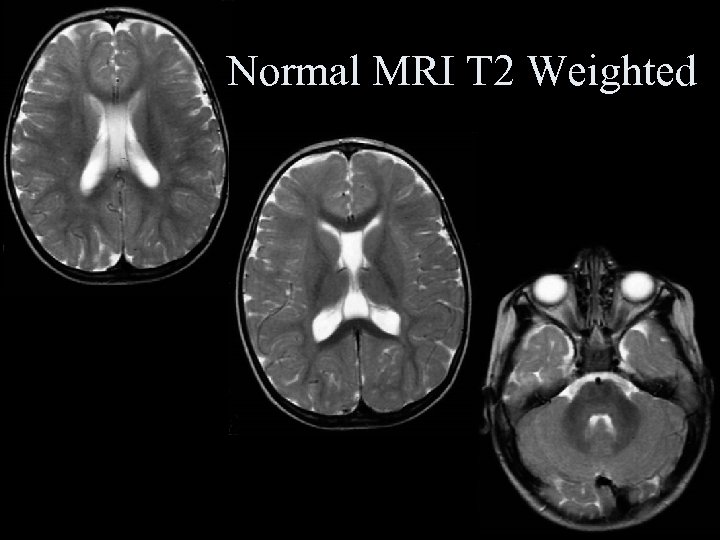

Normal MRI T 2 Weighted Normal MRI T 2 Weighted